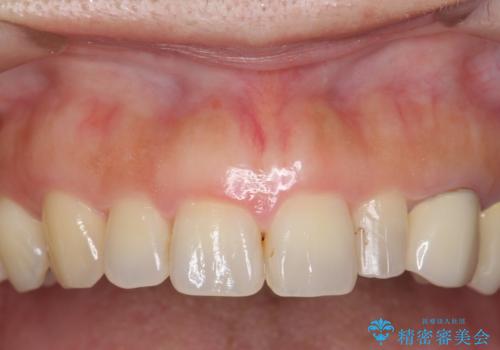

前歯が左右対称じゃない 保険の被せ物をきれいにしたい ホワイトニング併用

- 左上の前歯が小さく左右対称ではないのと、保険の前歯の被せ物のやりかえを希望して来院。

小さい前歯は、反対側と合わせた形にしました。

左右対称に仕上げることができ、治療には非常に満足していただきました。